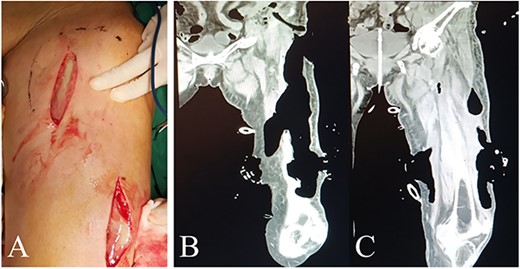

The first surgery was performed several hours after admission, aiming to debride necrotic tissue and pus for infection control, and to take tumor specimens for pathological examination. Multiple longitudinal incisions were made for drainage to avoid the perforators being damaged, which may lead to extensive skin necrosis in the blood supply area. During the surgery, a large amount of pus and gas overflowed from under the skin of the whole thigh and each intermuscular space with distinct stench of dung (Fig. 2A). Extensive necrosis was found in the subcutaneous fat fascia and the intermuscular fascia. Pus samples were taken for drug sensitivity test and bacterial culture. Blunt dissection was performed carefully and necrotic tissue under direct vision was excised, followed by repeated irrigation with huge amount of hydrogen peroxide and normal saline.

Intraoperative view and postoperative CT of left thigh in the first operation. (A) Intraoperative anterior view of left thigh. (B) and (C) Coronal planes from CT 7 days after the first operation display areas dressed with VSD (PU) material.

An infection pathway of about 3*2 CM at the inguinal posterior peritoneum invagination into the posterior peritoneal cavity was found and then widen by about 2 CM. The posterior peritoneal cavity was also irrigated with hydrogen peroxide and normal saline repeatedly using syringes in order not to injure peripheral vessels. Large quantity of pus was drained without distinct fecal residue, so we considered a small pore size of intestinal perforation. Pathological examination of posterior peritoneum was abandoned for limited vision. The drainage tubes were placed, and polyurethane (PU) were positioned as vacuum sealing drainage (VSD) material in the intermuscular spaces of left thigh and groin, and the posterior superficial peritoneum, respectively (Fig. 3). The wounds were sealed with films and connected to a vacuum source for creating negative pressure.